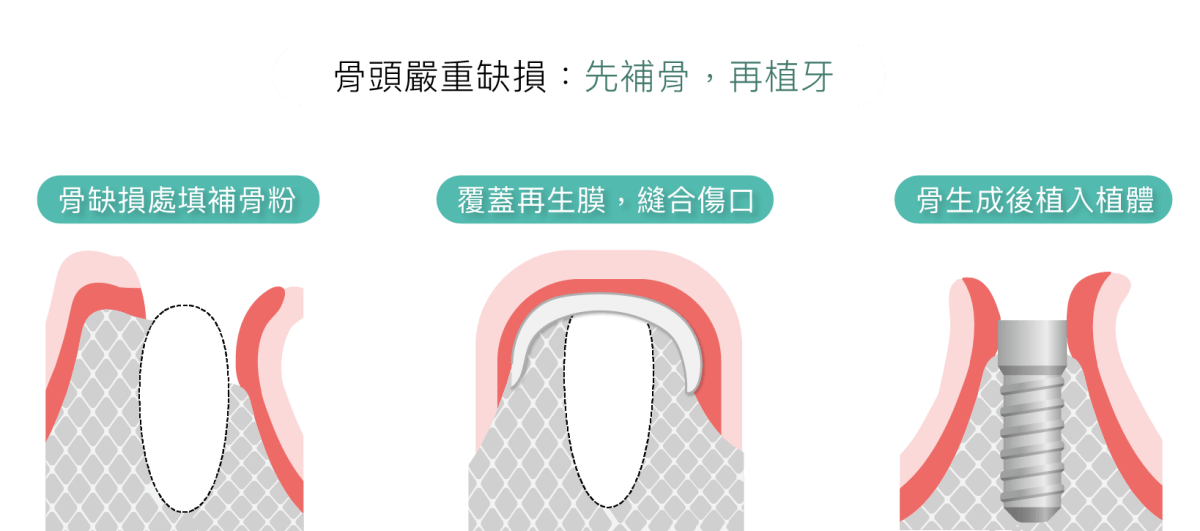

但如果骨頭缺失的情況已經較為嚴重,則建議先做一次補骨粉手術,骨粉的功用是誘導骨頭再生,依照每個人體質的不同,在術後約需4~6個月的時間,等骨粉刺激齒槽骨細胞,再生骨質,讓齒槽骨恢復原有寬度、高度、密度,再開始植牙療程。

將人工骨粉或是骨塊,置入齒槽骨,補骨粉會建立一個架構,讓自體骨質細胞沿著生長。齒槽骨萎縮嚴重者,須等待骨頭新生完整,才能進行植牙;輕微者,植牙、補骨可同時進行。

補骨粉是透過不同來源的骨粉填充,刺激骨質生長,而每位患者骨質生長狀況不同,骨粉的來源也可能影響生長速度。一般來說,補骨粉後需要等待3-6個月不等的時間,骨質才會生長出一定的量,達到接下來可施作植牙的骨質長寬高標準。